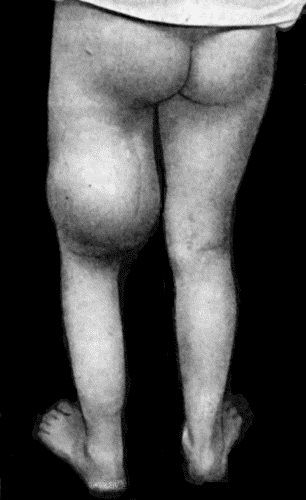

Typically a sarcoma was a large tumor that would grow out of the deep tissues in the leg (see historical picture from 1816 here and from 1920 here).